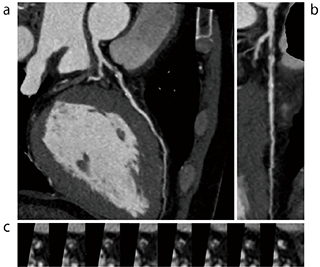

・心エコー検査では、左室機能が正常の症例でもEFが50%前後の低値を示すことが多く、臨床では注意を要する。図4は極端な例であるが、心エコーでのEFは68%、CTでは48%となっている。

図4 CT心機能解析2での抽出結果

a:拡張期(ED) b:収縮期(ES)

心筋の抽出精度が高く正確にトレースできている。